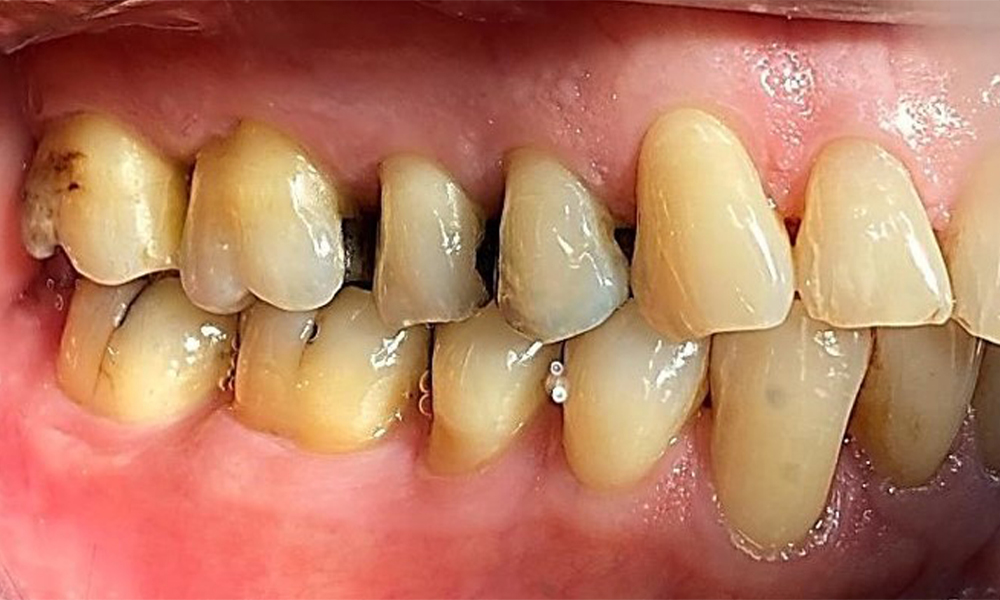

Right lateral view. Loss of the interdental papillae.

Fig. 3 Right lateral view. Loss of the interdental papillae. © Dr R. Krapf

Left lateral view including the recessions.

Fig. 4 Left lateral view including the recessions. © Dr R. Krapf

The patient has stage II, grade B periodontitis (5). At 1 to 3 mm, the clinical probing depths were within the physiological range. Localized probing depths of 5 mm were observed on the mesiopalatal aspects on both 17 and 27. There are generalized recessions of 1–3 mm with partial loss of the interdental papillae (Fig. 2, Fig. 3, Fig. 4)